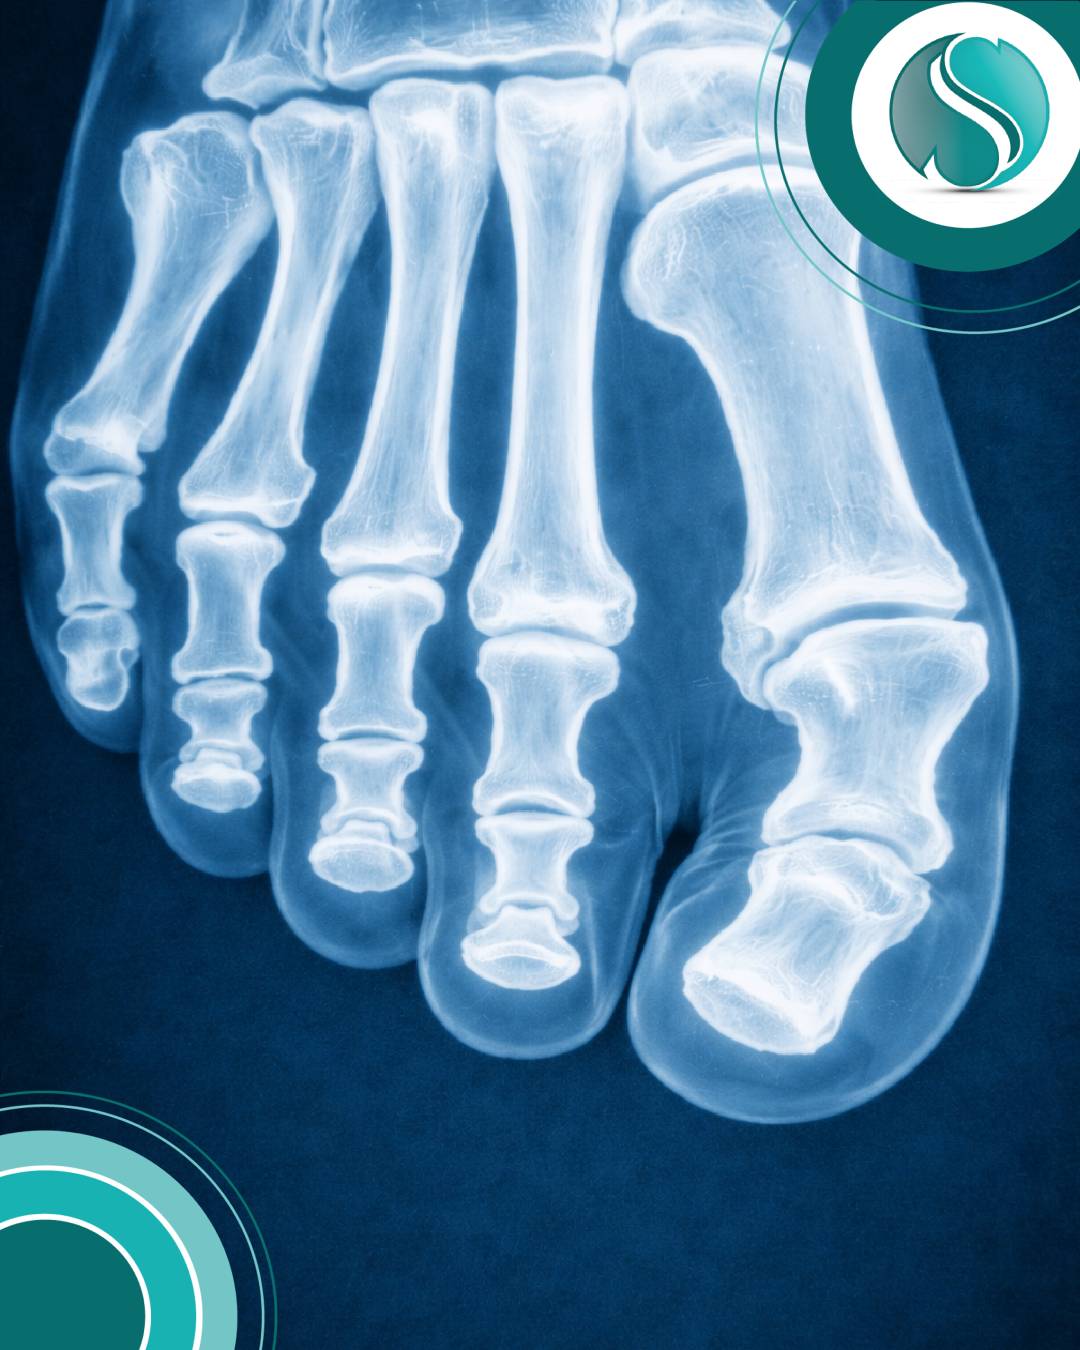

Beim Spreizfuß senkt sich das Quergewölbe des Vorfußes ab. Dadurch verbreitert sich der Vorfuß, und es kann zu belastungsabhängigen Beschwerden kommen – insbesondere beim Gehen und Stehen. In Ruhe lassen…